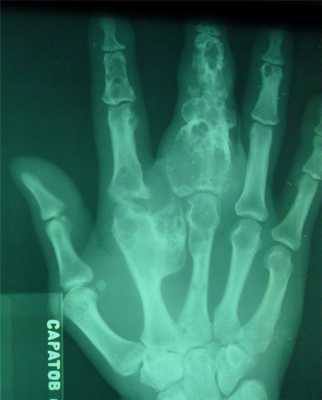

Гигантоклеточная опухоль

(остеобластокластома)

- состоит из клеток 2 типов- многоядерных гигантских и мелких одноядерных,

- поражаются люди в возрасте от 20 до 40 лет,

- локализация бедренная кость - дистальный конец, проксимальный конец б/берцовой кости, дистальный конец лучевой кости. Из плоских костей - тазовые кости и лопатка, очень редкая локализация в позвонках,

- одиночность и изолированность поражения,

- характерно расположение опухоли в эпиметафизраном отделе, который значительно вздут и деформирован, имеет вид крупнобугристого полушария, булавы,

- опухоль доходит до суставного хряща и обрывается,

- растет во всех направлениях, но главный рост происходит вдоль длинной оси кости в сторону с/3 диафиза кости,

- поперечник опухоли может увеличивать нормальный диаметр опухоли в 3-5 раз.

- ячеистый тип - опухоль состоит из отдельных камер, отделенных друг от друга полными и неполными перегородками (мыльные пузыри или неправильные соты),

- корковое вещество раздвигается, вздувается изнутри, истончается, надкостничных наслоений нет,

- при больших опухолях корковое вещество рассасывается и опухоль окружена со всех сторон тонкой скорлупой состоящая из стенок поверхностно расположенных ячеек.

- остеолитический тип - полное отсутствие ячеистого или трабекулярного рисунка, дефект кости вполне гомогенен,

- краевой блюдцеобразный дефект,

- корковый слой на пораженном месте рассасывается, а на границе с дефектом корка заострена, не подрыта и не имеет никаких периостальных наслоений,

- контуры дефекта резкие,

- патологические переломы в 12% случаев.